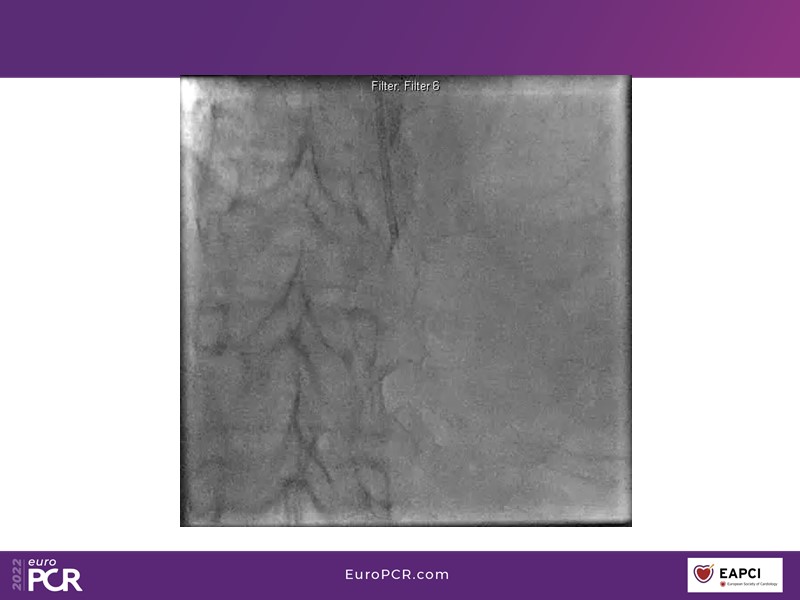

- To find out more about the application and mechanism of a sirolimus coated balloon for coronary artery disease treatment with case presentations in complex settings